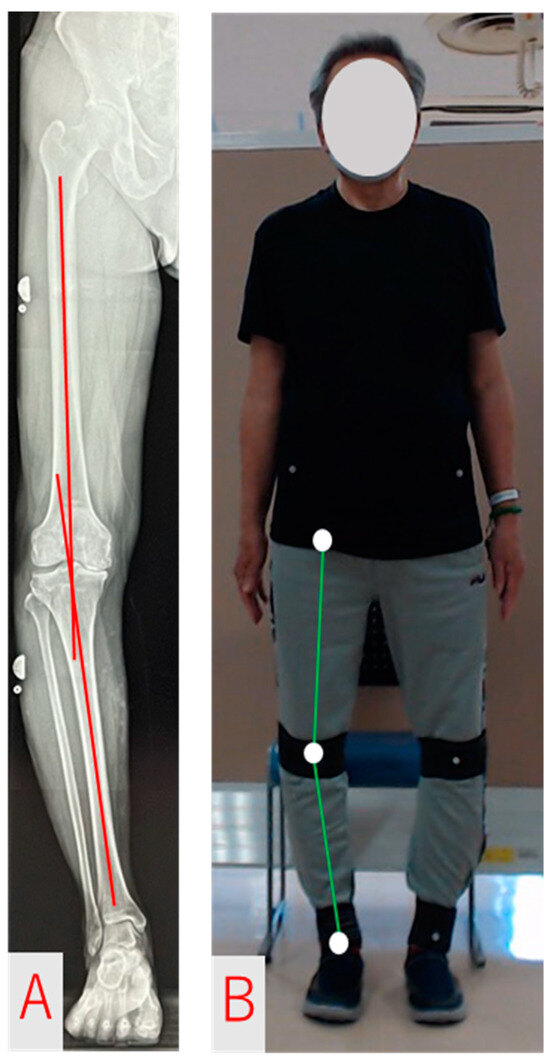

2.3. FTA Measurement and Analysis Methods